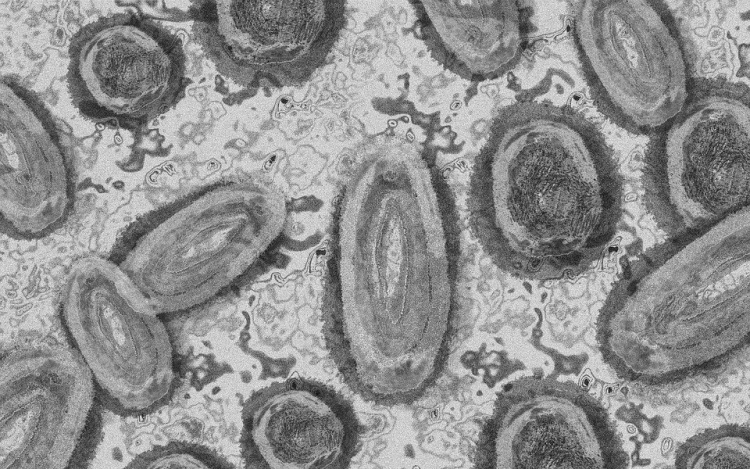

Tovább nőtt a majomhimlő-fertőzöttek száma Magyarországon

Újabb kilenc, 23-50 éves férfinél igazolták a majomhimlő-fertőzést Magyarországon, ezzel 42-re nőtt a fertőzöttek száma - közölte a Nemzeti Népegészségügyi Központ (NNK) csütörtökön az MTI-vel.